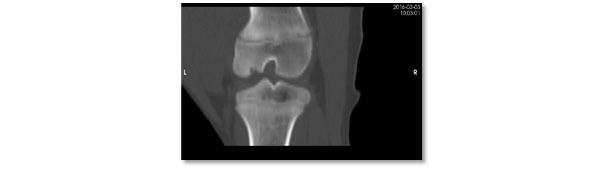

L'osteocondrosi (OC) è una condizione degenerativa e non infettiva delle articolazioni che ha una componente ereditaria. La patogenesi inizia con la condronecrosi ischemica che progredisce verso un'ossificazione anomala e possibili fratture della cartilagine articolare. Si potrebbe ritenere che vi sia un'opportunità di miglioramento nella causa iniziale (80% di prevalenza tra 8 e 12 settimane di età) o in progressione (con recupero del 60-70% a 25 settimane di età). Tuttavia, l'eziologia non è chiara (Olstad et al., 2015) e potrebbe includere traumatismi o fragilità del collagene (Laverty and Girard, 2013; Finnøy et al., 2017). Inoltre, la selezione genetica dovrebbe essere applicata per ridurre la prevalenza della OC, anche se inizialmente potrebbe essere difficile, poiché il potenziale di crescita in carnosità è geneticamente associato alla OC (Aasmundstad et al., 2013). D'altra parte, altri fattori che potrebbero influenzare la progressione della malattia sono poco conosciuti.